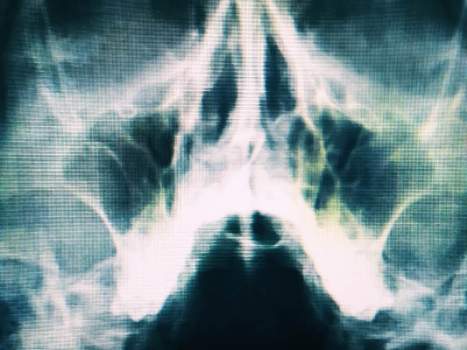

Пациент был направлен на рентгенографию ППН (придаточных пазух носа). На рентгенограмме выявлен уровень жидкости в верхнечелюстной паухе слева.

На снимке уровень жидкости, до лечения

Лечение шло с положительной динамикой, и уже через неделю, на повторной рентгенограмме ППН сохранялся лишь незначительный пристеночный отек.

Снимок, сделанный после лечения